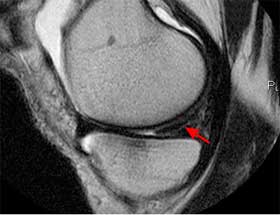

- Η Μαγνητική Τομογραφία MRI βοηθά στο να αναδειχθούν βλάβες στους μηνίσκους, τους συνδέσμους, τους χόνδρους και τα υπόλοιπα μαλακά μόρια. Η Μαγνητική Τομογραφία έχει 75-95% ακρίβεια στην ανάδειξη των μηνισκικών βλαβών.